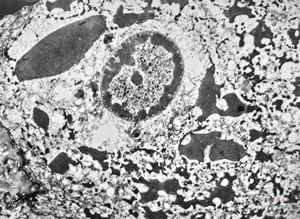

M, 11y. | mycosis fungoides v.s. - cerebriform nucleus of Sézary cell